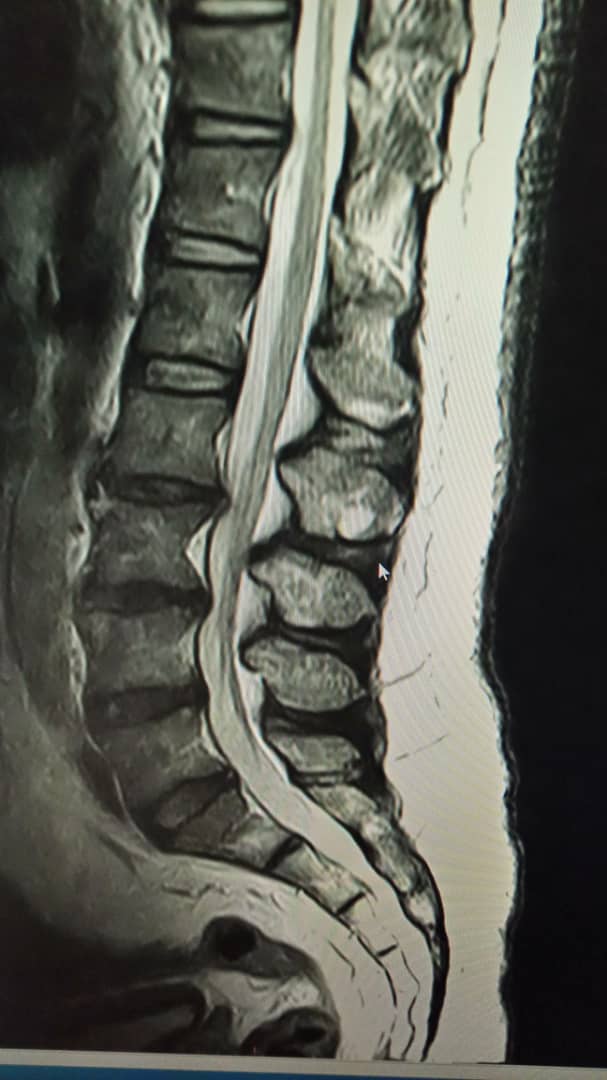

Our back is like the way we build houses.Block/cement/block/cement.

There are 5 bones in the lower back with 5 shock absorbers.

A Doctor’s job is to take a good history and do a full clinical examination. Thereafter, he can order blood tests,xrays,ct scan or an MRI scan to determine what is wrong,where, and plan what to do next.